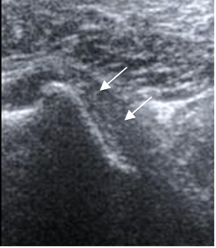

Fig 9. Tendón del subescapular normal.

Ecografía vista axial.